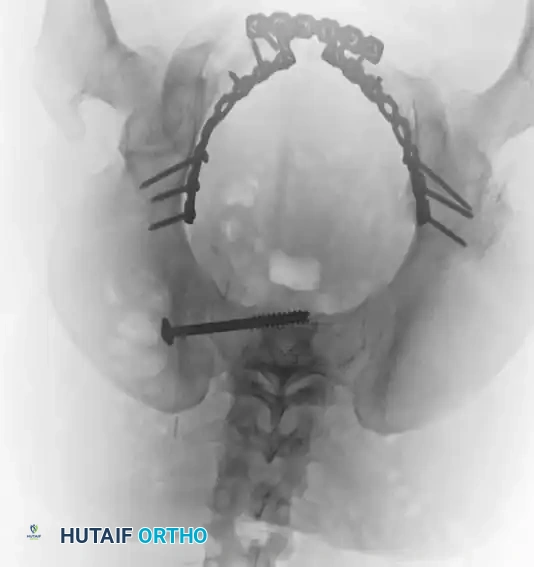

The following gallery demonstrates the progression of complex pelvic ring reconstructions, highlighting advanced imaging, intraoperative fluoroscopy, and definitive fixation constructs.

Definitive Fixation Constructs

Image